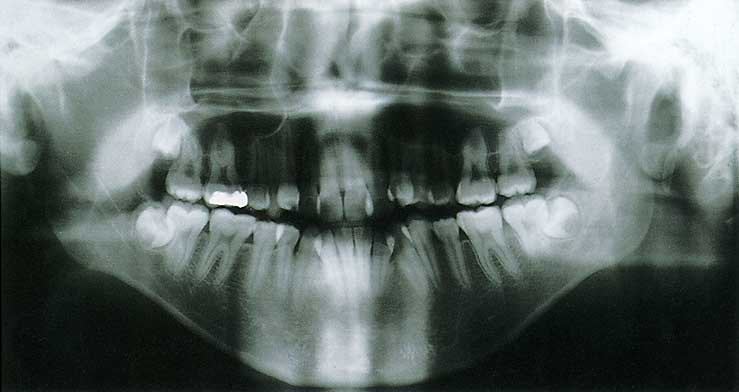

現代高校生男子(とくに細面)の歯列展開写真

(資料提供・新潟大学歯科矯正学教室)